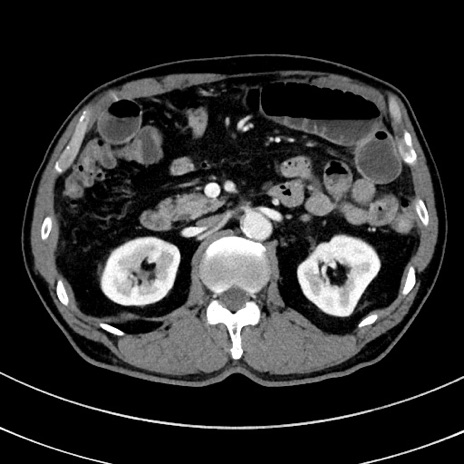

冠状断像

【症例】 60歳代男性

【主訴】 黒色吐物

【現病歴】 4日前から嘔気自覚、2日前の朝食後にも嘔気あり、自分で手で嘔吐反射起こし嘔吐したところ血が混ざっていたため受診。

【既往歴】 5年前汎発性腹膜炎を伴う急性虫垂炎で手術、高血圧、前立腺肥大症、高脂血症

【身体所見】 腹部正中に手術癩痕あり 腹部平坦・軟圧痛なし膨満感あり

【データ】WBC 8400、CRP 4.54